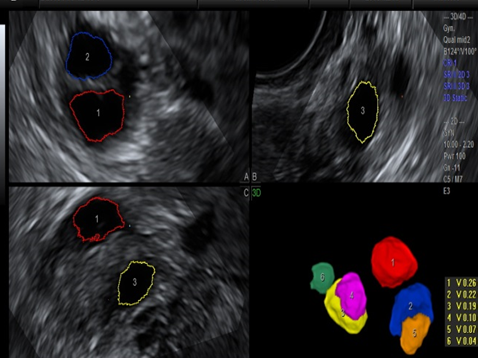

卵巢容积成像

也就是4D超声波技术,是目前世界上最先进的彩色超声技术。四维成像技术(4D),能直观、立体显示人体器官的三维结构及动态、实时地观察立体结构,而以往的二维成像技术只能显示人体器官的某一切面。